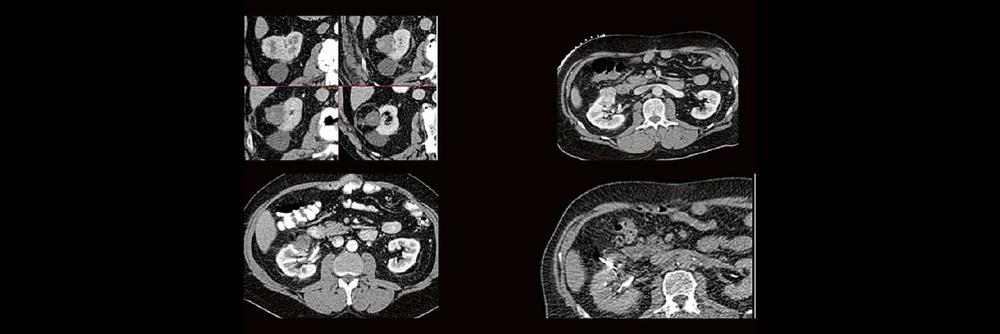

Dr. med. Sascha Alexander Pietruschka Die Anwendung von ablativen Verfahren hat sich in der klinischen Praxis etabliert. Nierentumoren bieten sich für den Einsatz von RFA und Mikrowelle an. Im Dietrich Bonhoeffer Klinikum Neubrandenburg blicken wir auf 15 Jahre Erfahrung mit mehr als 100 RFA/Mikrowellenablationen von Nierentumoren zurück. Im Vortrag werden die eigenen Erfahrungen und Ergebnisse

Thermoablation von Nierentumoren (Webinar | Online)Read More »